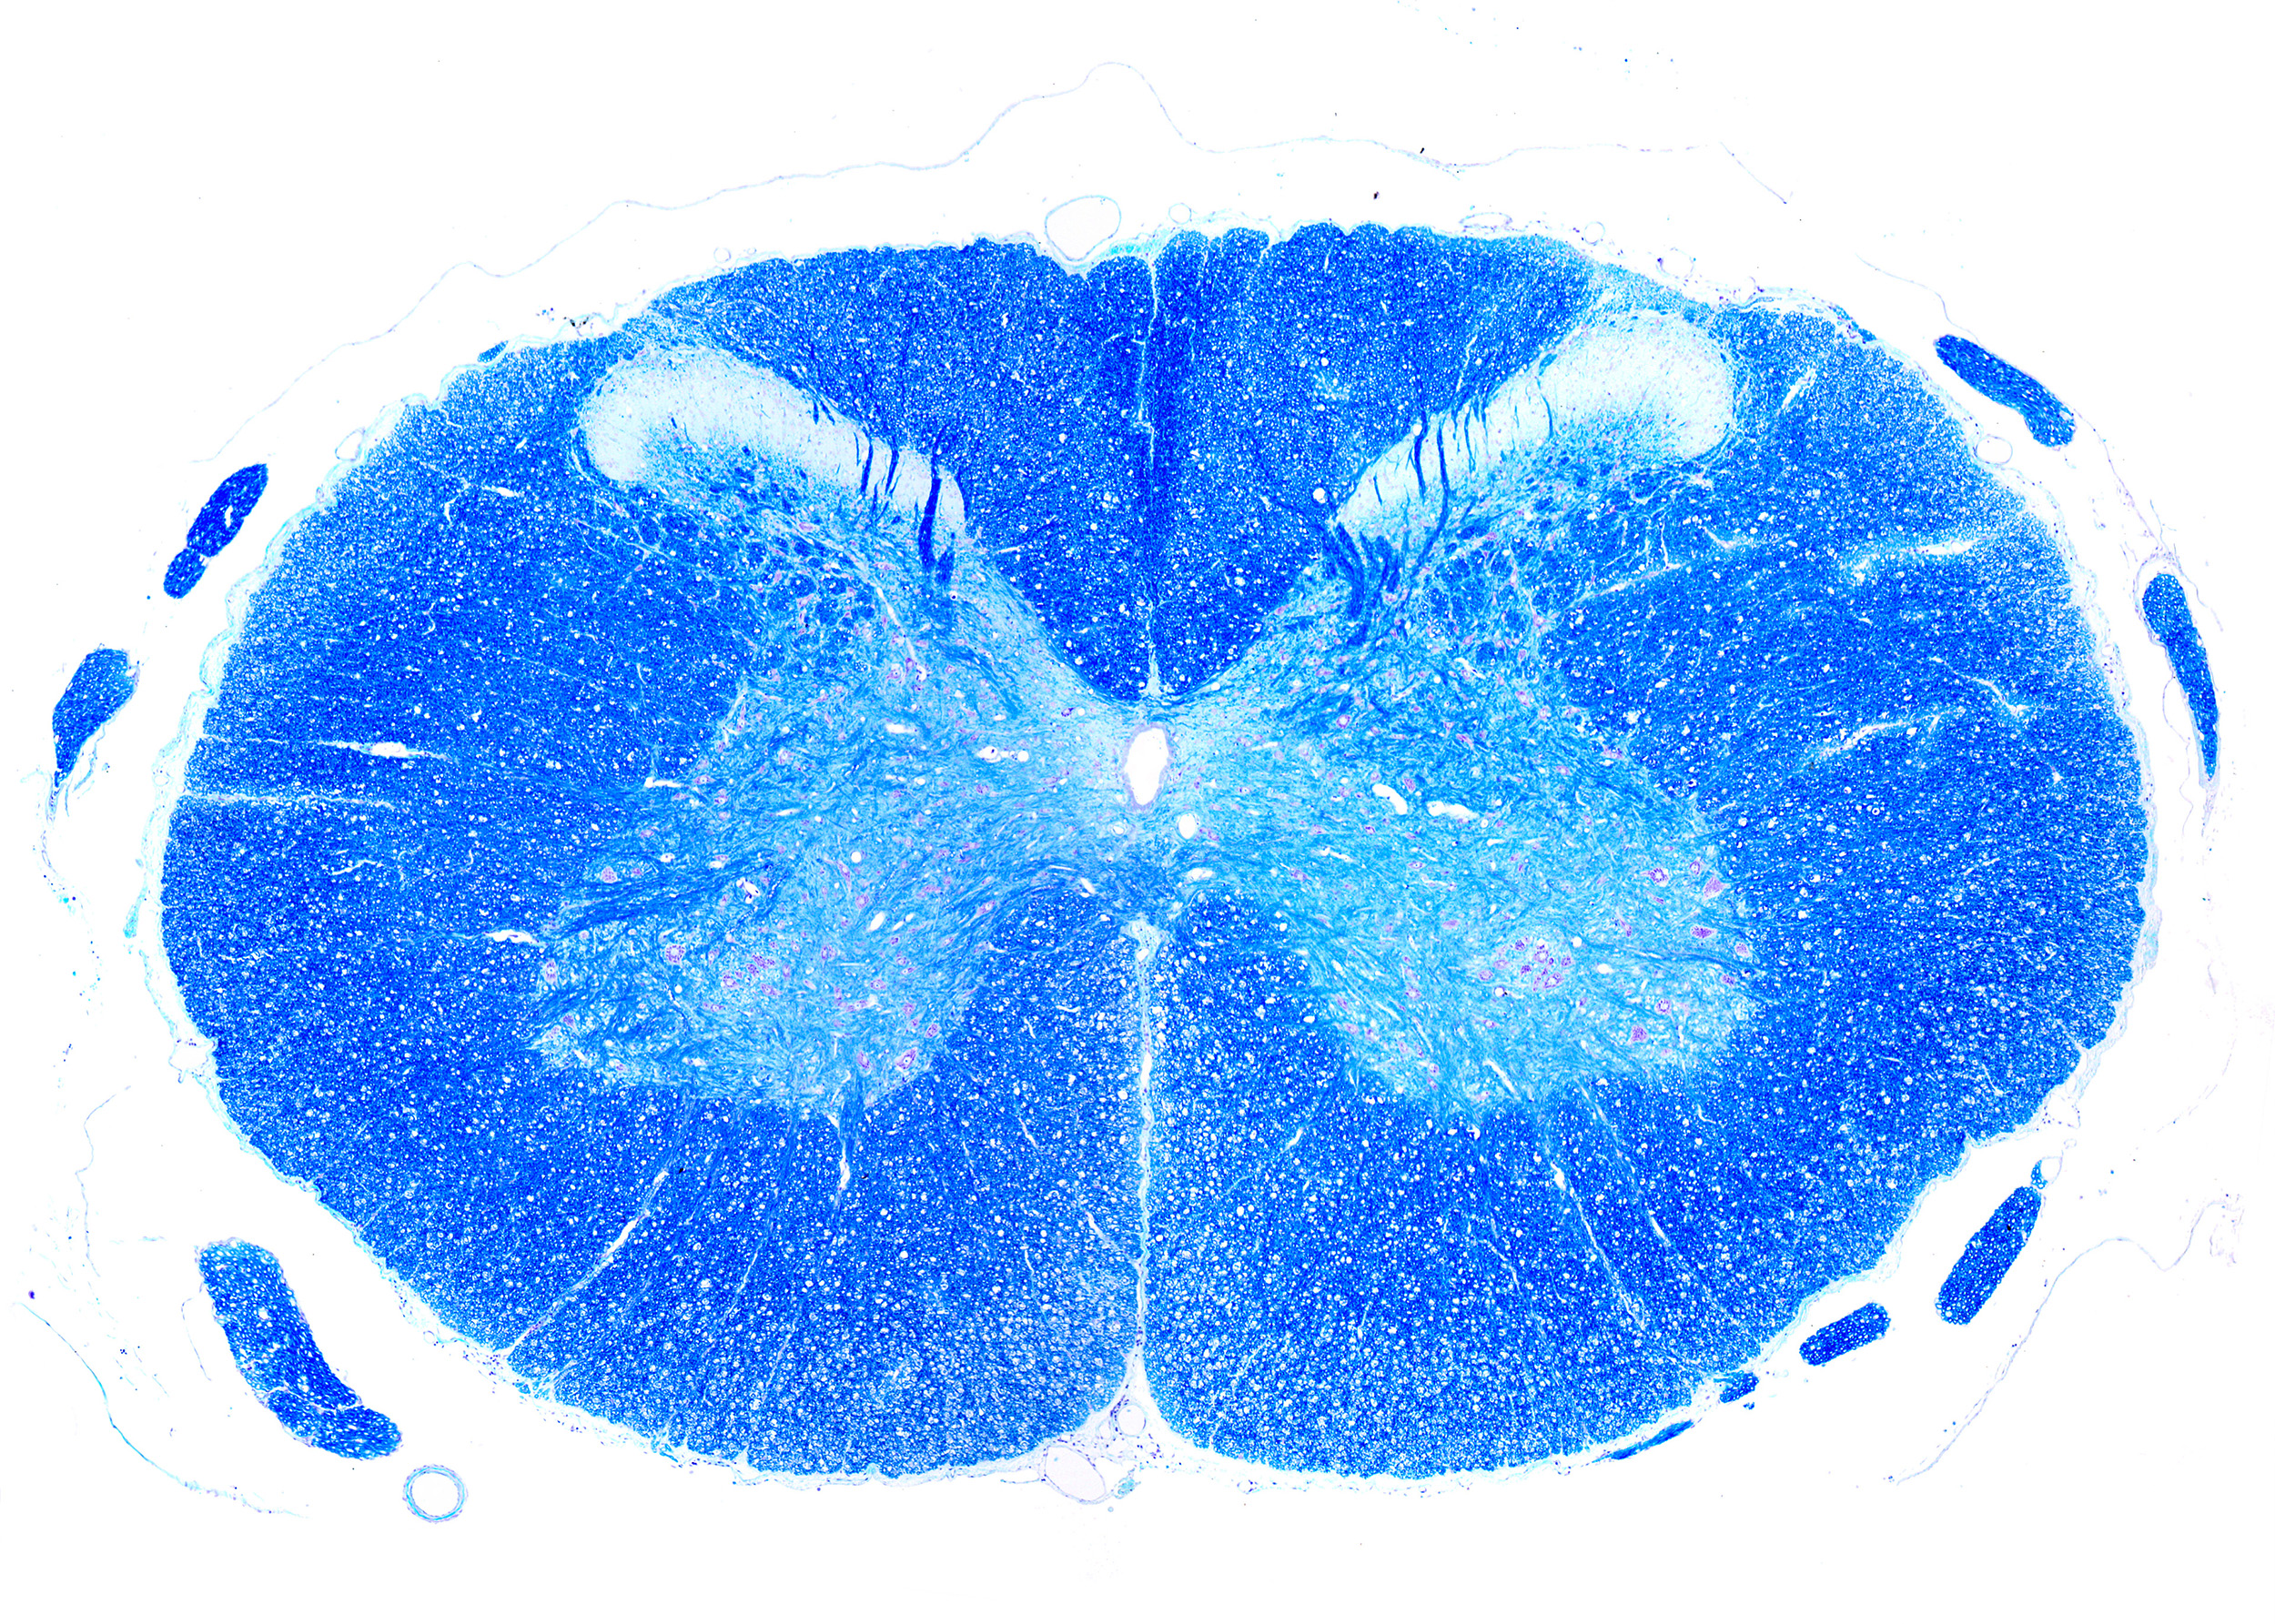

V přednášce se zaměříme na míchu a procesy, které nastávají po jejím poranění. Ukážeme si, že poranění míchy je dynamický děj, který probíhá v několika fázích – akutní, subakutní a chronické – a každá z nich má svá specifika. Do hry vstupuje imunitní systém, změny ve stabilitě neuronů, reakce podpůrných buněk i proměny extracelulární matrix, v níž se buňky míchy nacházejí. Výsledkem je nová rovnováha mezi buněčnými a mezibuněčnými složkami míchy, která vede k funkčnímu deficitu.